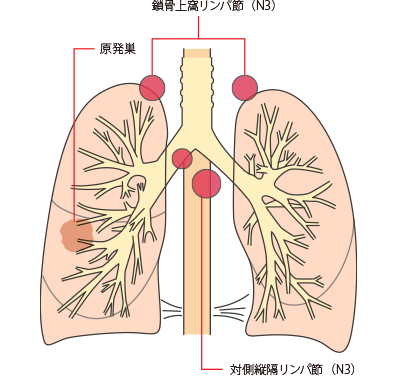

N3

対側縦隔、対側肺門、同側あるいは対側の前斜角筋、鎖骨上窩リンパ節への転移

N3は、原発巣とは反対側の縦隔リンパ節や肺門リンパ節または鎖骨上のリンパ節、首の付け根にあるリンパ節に転移があることです。

IIIB・IIIC期(ステージ3):局所進行がん

IIIB期

IIIC期

TNM分類でⅢB・ⅢC期と分類された肺がんは、ⅢA期よりさらに進行した状態の局所進行がんとされています。原発巣側の肺外にリンパ節転移が生じています(N2またはN3)。手術ですべてを取り切ることは難しく、手術をしてもがんが残ってしまう可能性が高いことから、基本的に手術はおこないません。